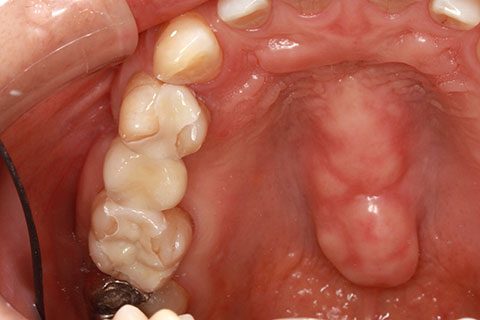

• オールセラミックの症例2

治療前

治療後

年齢・性別

45歳男性

治療期間

2ヶ月

抜歯

なし

治療費

70.4万円

備考

前歯8本の歯列不正によるセラミック治療

治療内容

歯質を削除し、セラミック冠をセメント合着

施術の副作用(リスク)

知覚過敏、歯髄炎、荷重負担